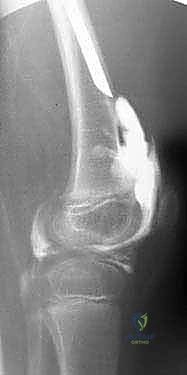

- تشوهات الركبة: غياب أو نقص تنسج الأربطة الصليبية (ACL & PCL)، مما يسبب عدم استقرار في مفصل الركبة.

2. قطع عظم ديجا (Dega Osteotomy)

في الحالات التي يكون فيها الحق (تويج الحوض) ضحلاً ولا يغطي رأس الفخذ بشكل كافٍ (Hip Dysplasia)، يجري الدكتور هطيف عملية "ديجا". يتم فيها عمل شق في عظام الحوض وثنيه للأسفل لتكوين سقف متين يغطي رأس الفخذ، ثم يتم وضع طعم عظمي لتثبيت الوضع الجديد. هذا الإجراء ضروري لمنع خلع الورك أثناء عملية التطويل اللاحقة.